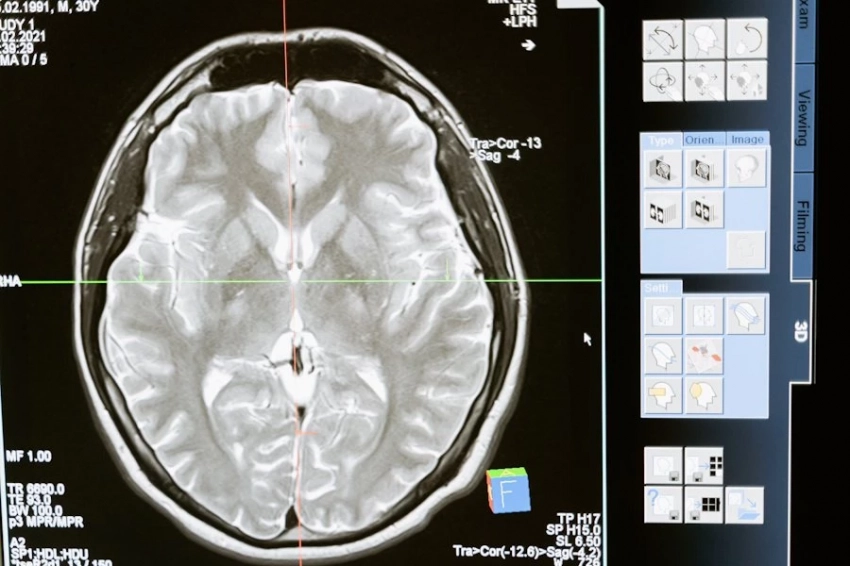

Согласно исследованию, МРТ-сканирование показало, что у людей с заболеваниями десен наблюдаются измененные связи между различными областями мозга по сравнению с людьми с хорошим здоровьем зубов.

«Эти различия свидетельствуют о том, что пародонтит может негативно влиять на функцию мозга даже при нормальном когнитивном развитии», — пришла к выводу исследовательская группа под руководством Сайоху Ли из Аньхойского медицинского университета в Хэфэе (Китай).

Исследователи утверждают, что у людей с заболеванием десен средней и тяжелой степени наблюдались изменения в связях между различными областями мозга и внутри них. В целом, заболевания десен были связаны с нарушением работы нейронных сетей в головном мозге.